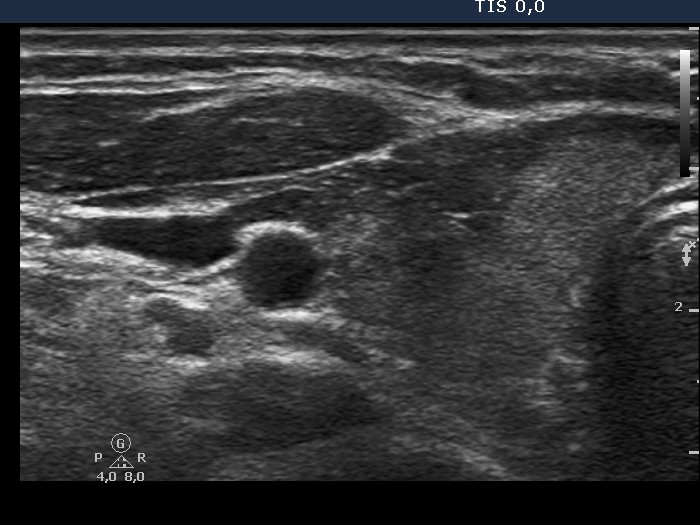

Right lobe, longitudinal scan

Right lobe, transverse view. There are several small hypoechogenic areas in echonormal background.